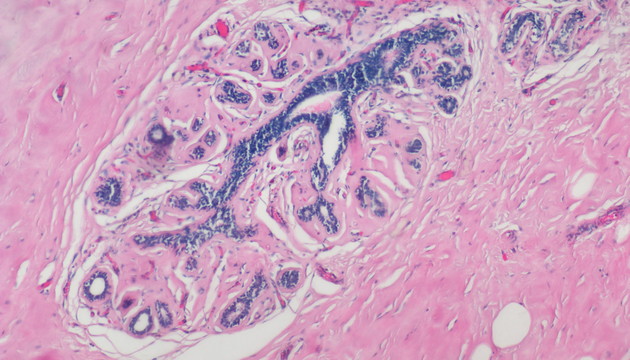

依據癌細胞在分子表達層面和細胞組織層面的變化,運用各類顯微成像技術對癌細胞進行篩選與識別,如①病理切片②免疫組化(IHC)③原位熒光雜交(FISH)④循環腫瘤檢測(CTC)⑤腫瘤細胞培養研究

癌癥研究中的成像有明場和熒光兩類,明場設備要求低,但病理切片全片判讀工作量大,效率低,使用切片掃描系統通過電動掃描和拼接軟件,實現高效全局成像與局部放大,可提升診斷精度與效率;多色熒光成像高靈敏度、高特異性,但信號弱,需優化激發光、濾光片、成像設備及圖像處理,以獲取清晰多通道信號;對于細胞培養,還有如何長時間成像監測,同時減少污染、不影響細胞生長的困難